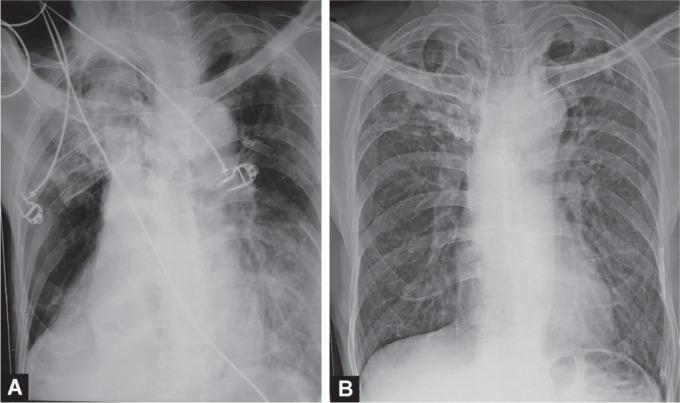

Endobronchial blood clots or mucus plugs can present with minimal symptoms or acute airway obstruction in the intensive care unit (ICU) patients. Acute airway obstruction can lead to rapid worsening of dyspnea owing to poor oxygenation due to collapse of the lung. Prompt recognition and treatment of this condition can translate into a successful outcome by decreasing morbidity and mortality and facilitating successful weaning of these patients. When conventional methods fail to relieve the obstruction, cryoextraction a novel technique, may prove to be a useful alternative for the removal of these clots and mucus plugs. Cryoextraction is best performed with rigid bronchoscopic intubation. However, in certain conditions, it may be used with a flexible fiberoptic bronchoscope (FOB) through an endotracheal tube, especially when bedside procedure is required in ICU patients. In this series, three cases are being discussed where bedside flexible bronchoscopy-guided cryoextraction was done leading to a successful resolution of acute hypoxemic respiratory failure. Tale S, Meitei SP, Prakash V, Negi A, Mishra M, Sindhwani G. Bronchoscopic Cryotherapy for Acute Hypoxemic Respiratory Failure in Three Mechanically Ventilated Patients: A Case Series. Indian J Crit Care Med 2021;25(1):94-96.

支气管内血凝块或黏液栓在重症监护病房(ICU)患者中可能表现为轻微症状或急性气道阻塞。急性气道阻塞可导致由于肺萎陷引起的氧合不良而使呼吸困难迅速加重。及时识别和治疗这种情况可通过降低发病率和死亡率并促进这些患者的成功脱机而带来成功的结果。当传统方法无法缓解阻塞时,冷冻提取这一新技术可能被证明是清除这些血凝块和黏液栓的有用替代方法。冷冻提取最好通过硬质支气管镜插管进行。然而,在某些情况下,它可通过气管内导管与可弯曲纤维支气管镜(FOB)一起使用,特别是在ICU患者需要床边操作时。在本系列中,讨论了3例床边可弯曲支气管镜引导下冷冻提取成功解决急性低氧性呼吸衰竭的病例。Tale S, Meitei SP, Prakash V, Negi A, Mishra M, Sindhwani G. 三名机械通气患者急性低氧性呼吸衰竭的支气管镜冷冻治疗:病例系列。《印度危重症医学杂志》2021年;25(1):94 - 96。